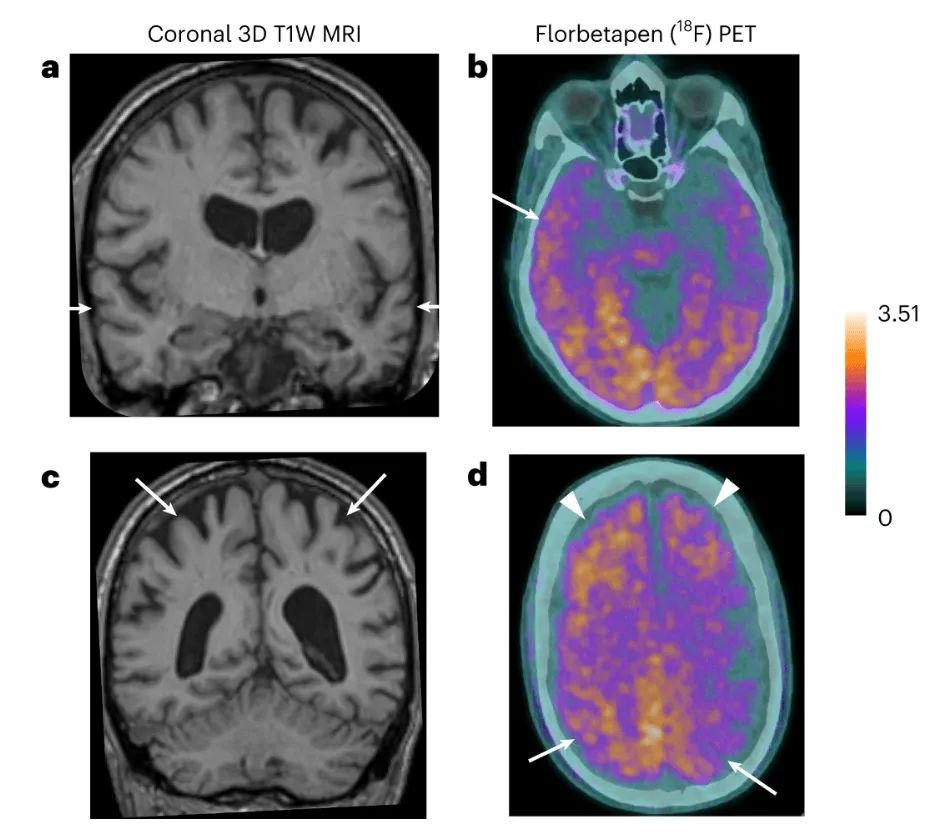

En el nuevo estudio, los científicos describen a ocho personas del Reino Unido que habían recibido c-hGH de niños pero que no desarrollaron la ECJ. Cinco de estos pacientes presentaban síntomas compatibles con una demencia de inicio precoz (38-55 años) que cumplían los criterios diagnósticos del alzhéimer, con un deterioro progresivo en dos o más dominios cognitivos lo suficientemente grave como para afectar a la realización de sus actividades habituales de la vida diaria.

Los análisis de biomarcadores, que no pueden utilizarse para diagnosticar la enfermedad en ausencia de síntomas, apoyaron el diagnóstico de alzhéimer en dos de las personas diagnosticadas con la afección, y fueron sugestivos de enfermedad en otra persona.

Los autores también realizaron estudios de autopsia en dos pacientes fallecidos durante el periodo de estudio, que incluyeron una amplia toma de muestras de tejido cerebral; y uno de estos pacientes también mostraba la patología.